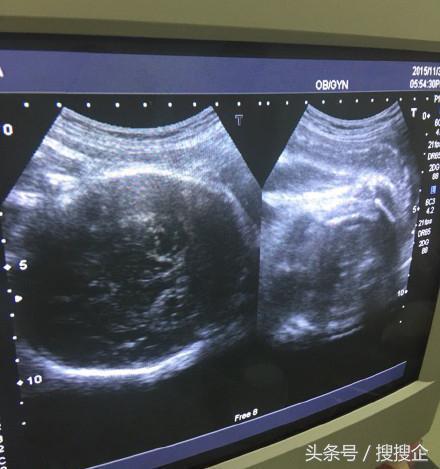

很多明星怀孕都会在社交平台晒一张B超单,证实自己怀孕。

比如范玮琪她家

比如林志颖他家

B超单是准妈妈与胎儿的第一次亲密接触,但也有很多准妈妈苦恼,并不清楚上面写的内容是什么意思?专业术语代表什么?怎么判断胎儿好不好? 其实B超单上的每一项指标都是对胎儿的基本情况,根据这些数据判断胎儿的发育状况和健康指数。接下来,打开你手中的B超单,跟小编做对照。